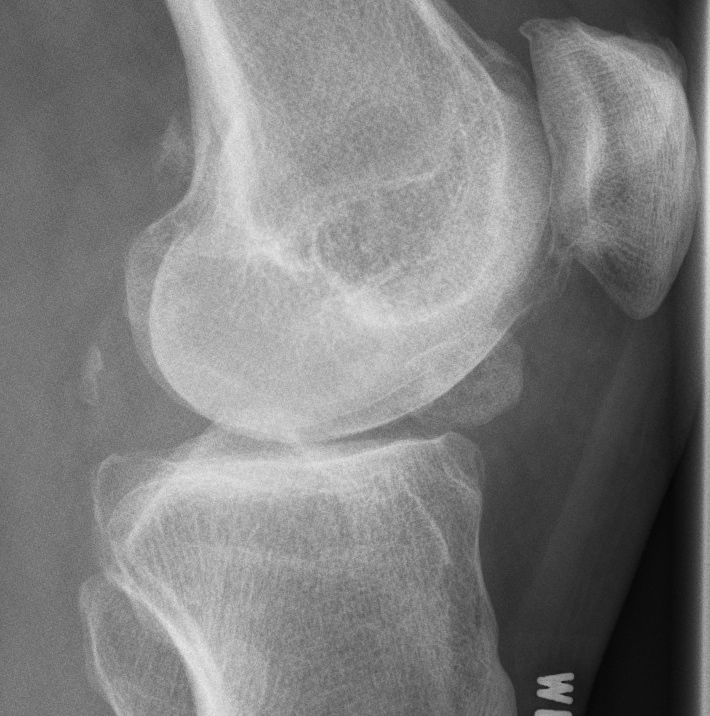

Xray

OA Loose Bodies

OCD Loose Bodies